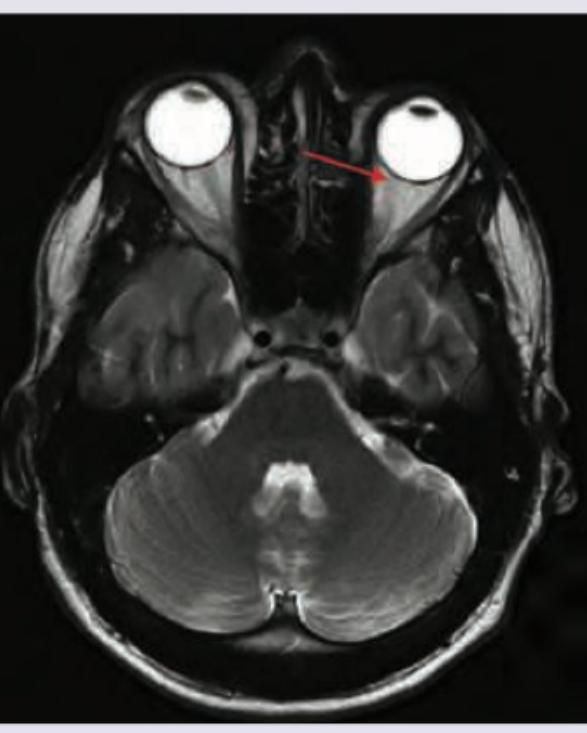

The marked extraocular muscle has a cranial nerve nucleus. At what level in the brain is the nucleus located? (AIIMS May 2018)

Explanation: ***Facial colliculus*** - The image shows the **lateral rectus muscle** (indicated by the arrow), which controls abduction of the eye. - The lateral rectus muscle is innervated by the **abducens nerve (CN VI)**, and its nucleus is located at the **facial colliculus** in the pons. - The facial colliculus is a bulge on the dorsal surface of the pons, formed by the **facial nerve (CN VII) fibers** wrapping around the **abducens nucleus (CN VI)**. - This is the only extraocular muscle whose nucleus is located at the facial colliculus. *Superior colliculus* - The superior colliculus is located in the **midbrain** and is involved in visual reflexes and saccadic eye movements. - The **oculomotor nucleus (CN III)** is located ventral to the superior colliculus in the periaqueductal gray at the level of the superior colliculus. - CN III innervates the superior rectus, inferior rectus, medial rectus, and inferior oblique muscles, but not the muscle shown in the image. *Superior olivary nucleus* - The superior olivary nucleus is located in the **pons** and is a critical component of the auditory pathway, involved in sound localization. - It has no role in the innervation of extraocular muscles. *Inferior colliculus* - The inferior colliculus is situated in the **midbrain** and is a major relay center in the auditory pathway. - The **trochlear nucleus (CN IV)** is located at the level of the inferior colliculus and innervates the superior oblique muscle. - However, the inferior colliculus itself does not contain nuclei for extraocular muscle innervation.